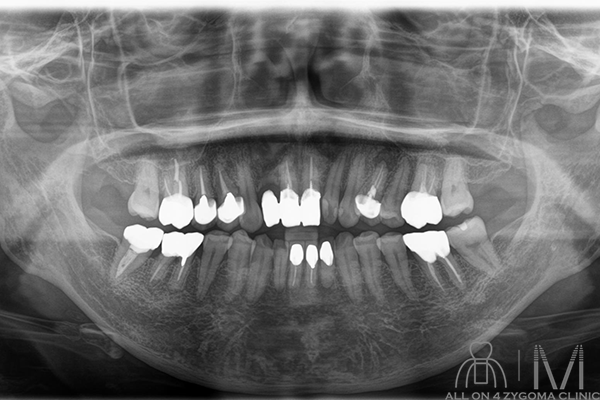

術前パノラマ画像所見

7-3 1┴1-7は残存歯、2┘は欠損。6541┴146は失活歯。5┴46はper様所見を認める。上顎は中等度~高度の水平性骨吸収を認める。7┴7で強い。両側上顎骨の異常吸収像を認める。 下顎は7-1┬1-7は残存歯。761┬126は失活歯。明らかな根尖病変を示唆する歯は認めない。軽度~中等度の水平性骨吸収を認める。